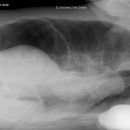

Abdomen

Ileus